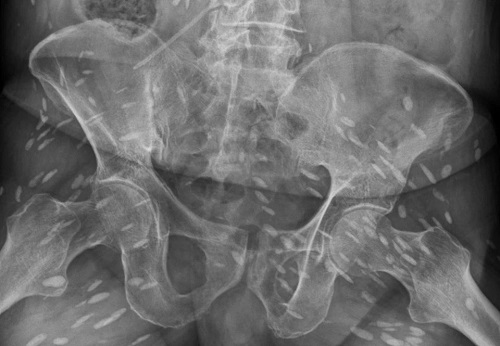

Hình ảnh phim chụp cho thấy chi chít trứng sán trong cơ thể người đàn ông 74 tuổi ở Đài Loan. Ảnh: The Sun |

Bệnh nhân được đưa đi kiểm tra toàn thân. Kết quả phim chụp CT, MRI và X-quang khiến các bác sĩ kinh hoàng khi phát hiện những ổ trứng sán dây nhỏ chi chít khắp cơ thể bệnh nhân: trong não, cột sống, vùng chậu, cổ, ngực, chân tay... Đây cũng chính là nguyên nhân khiến não bệnh nhân bị ảnh hưởng, gây ra tình trạng mất trí nhớ và không thể đi lại.